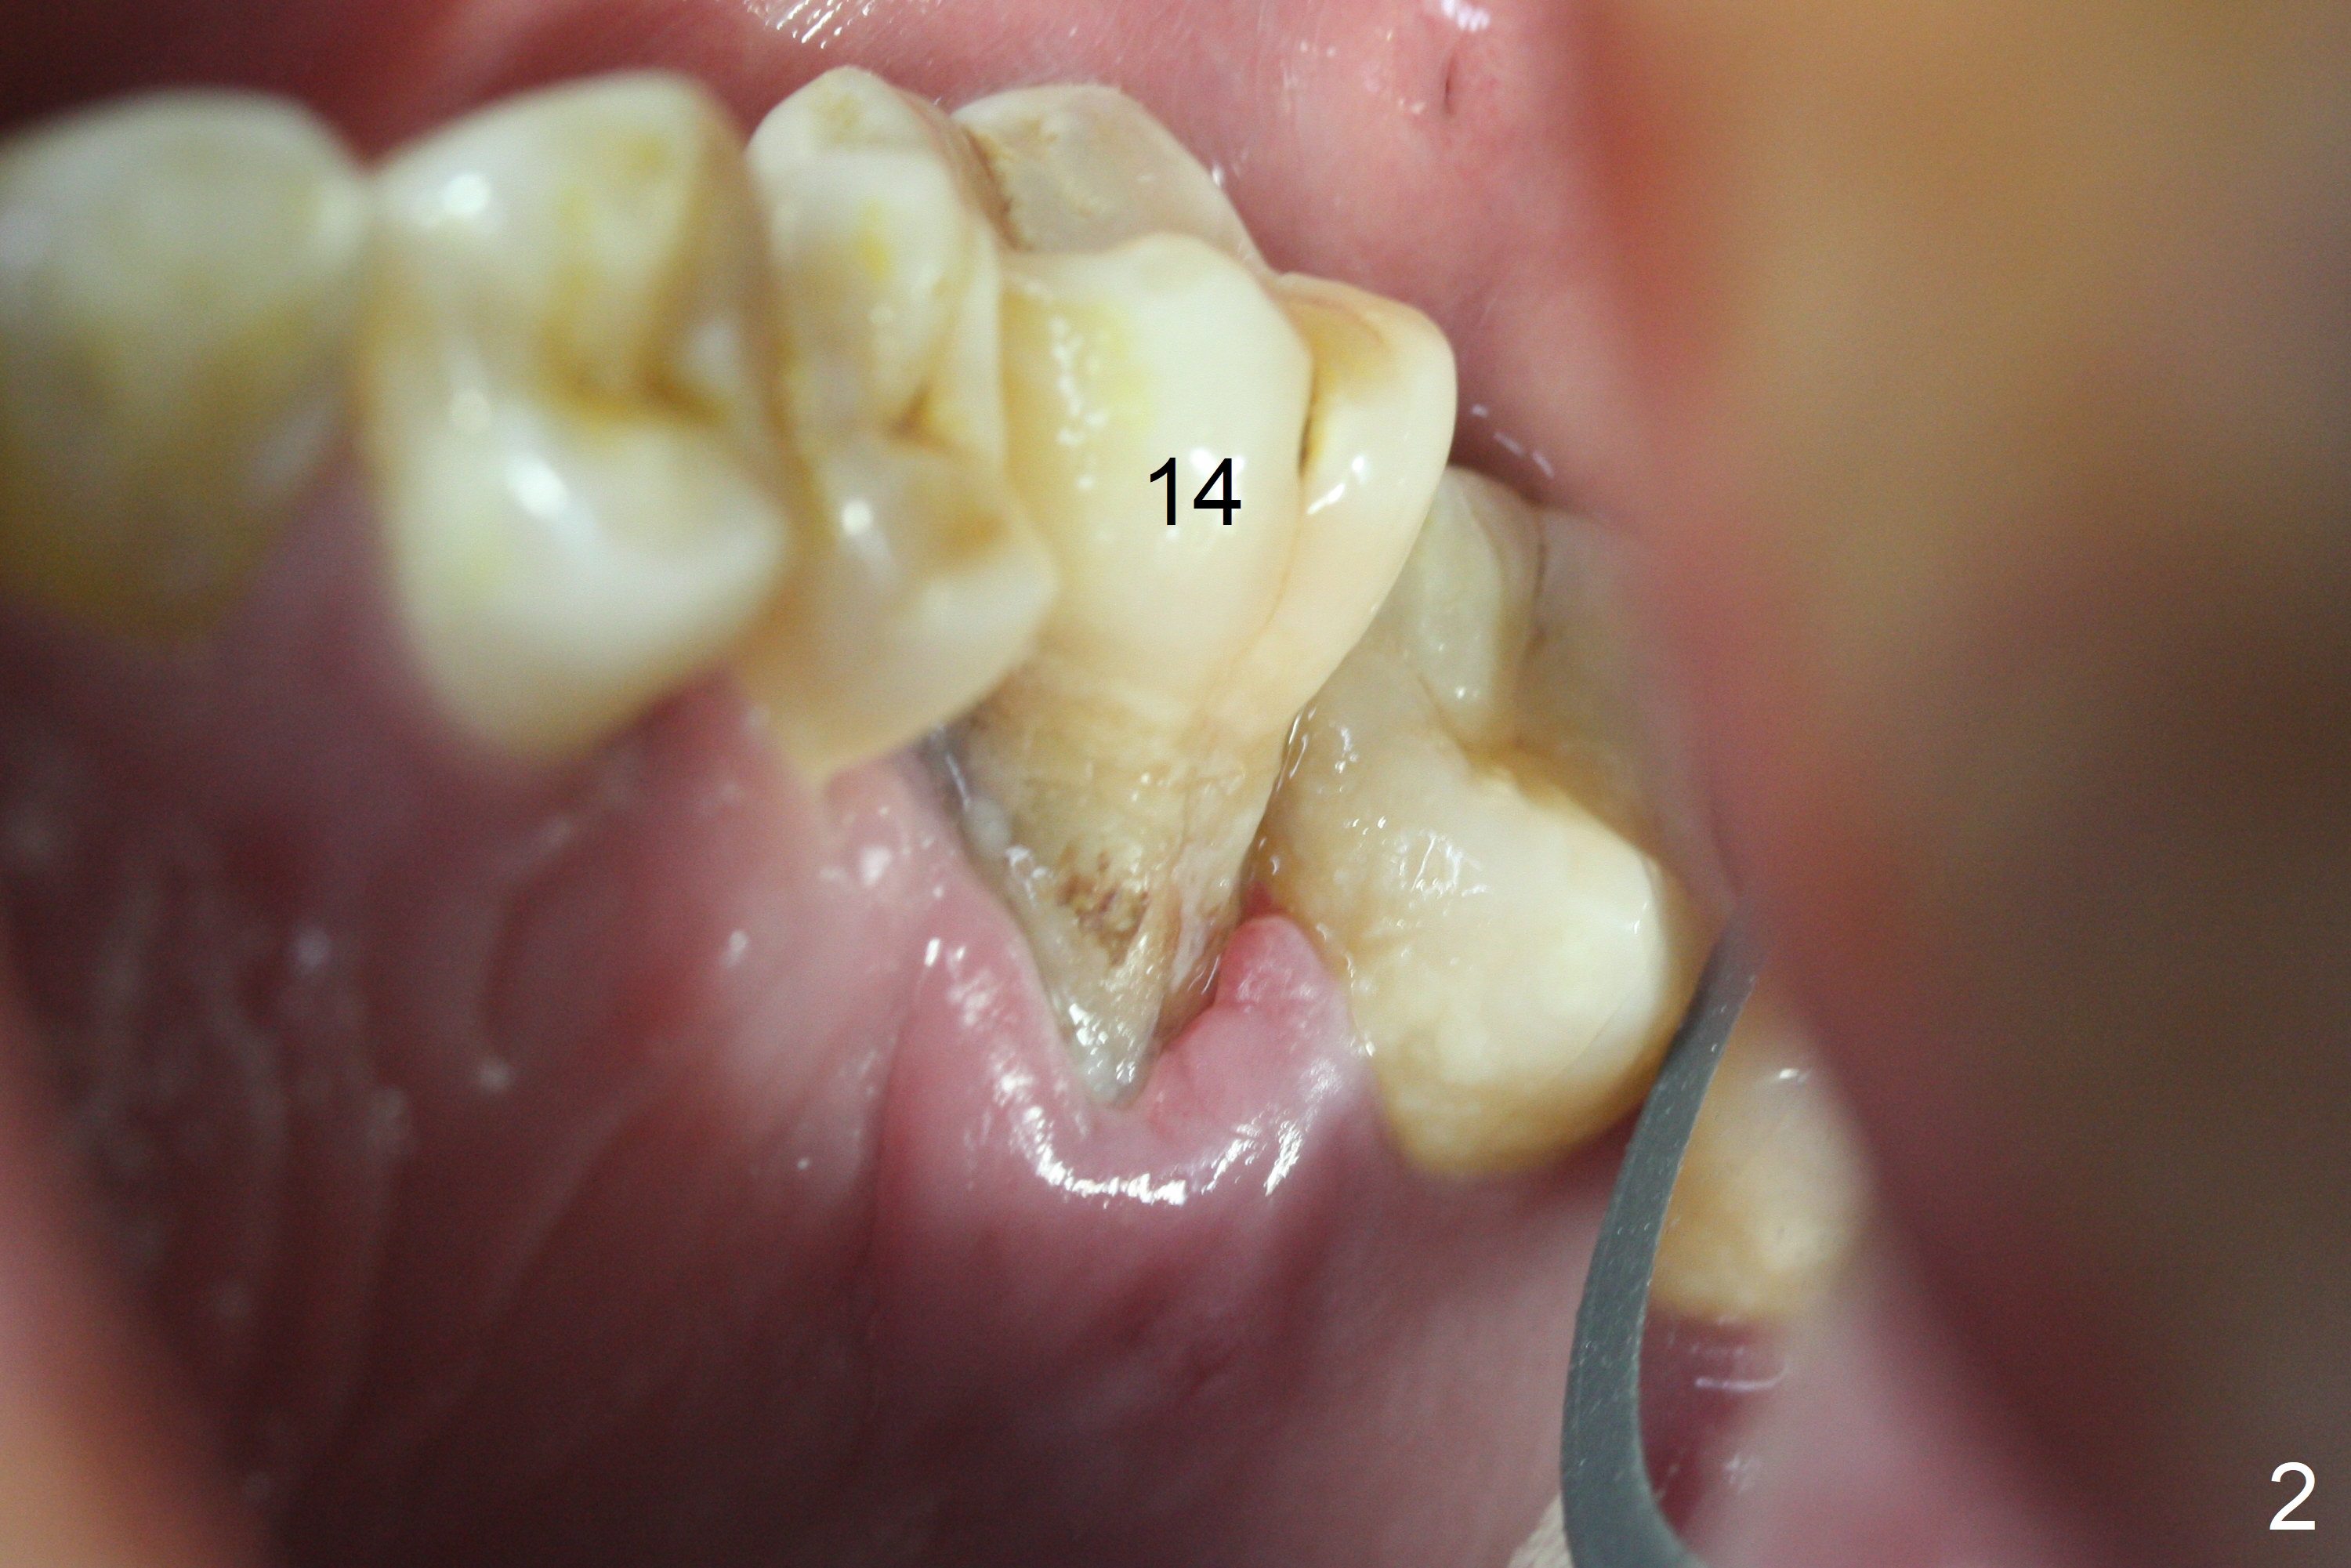

When the displaced tooth #14 (Fig.1) with palatal gingival recession (Fig.2) is extracted, the buccal plate is low, while the palatal one is lost.  Osteotomy is initiated in the bottom of the large socket with Marking Drill.  The bone turns bluish, suggesting thin bone (in fact less than 1 mm as well as low density).  Magic Sinus Lifter (Fig.3 *, Fig.4 blue area) is used for sinus lift (Fig.4 (red curved line: lifted sinus membrane; grey area: a portion of the lifted sinus floor), followed by insertion of a piece of PRF plug and Vanilla bone graft for sinus lift.  The osteotomy is enlarged lightly with 4.8 mm Magic Drill (compare black strips between Fig.4,5).  A 5x9 mm dummy implant (Fig.5 green) is dislodged into the sinus.  The lifted sinus membrane holds the implant in place.  The black thin strip in Fig.5 and black circle in Fig.6a (occlusal view) represents the osteotomy.  After increase in the osteotomy with Lindamann bur (Fig.6b red circle), the implant (Fig.6c green) is retrieved with endodontic forceps (Fig.6c two blue dots (beaks of the forceps); Fig.7,8).  With the enlarged osteotomy (Fig.6d), a 6x9 mm dummy implant is placed deep (Fig.9).  The definitive implant is 6.5x11 mm with insertion torque ~ 15 Ncm (Fig.10).  With placement of a healing screw and further placement of allograft (Fig.11 *), the socket is closed with PRF membrane and collagen plug (Fig.12).